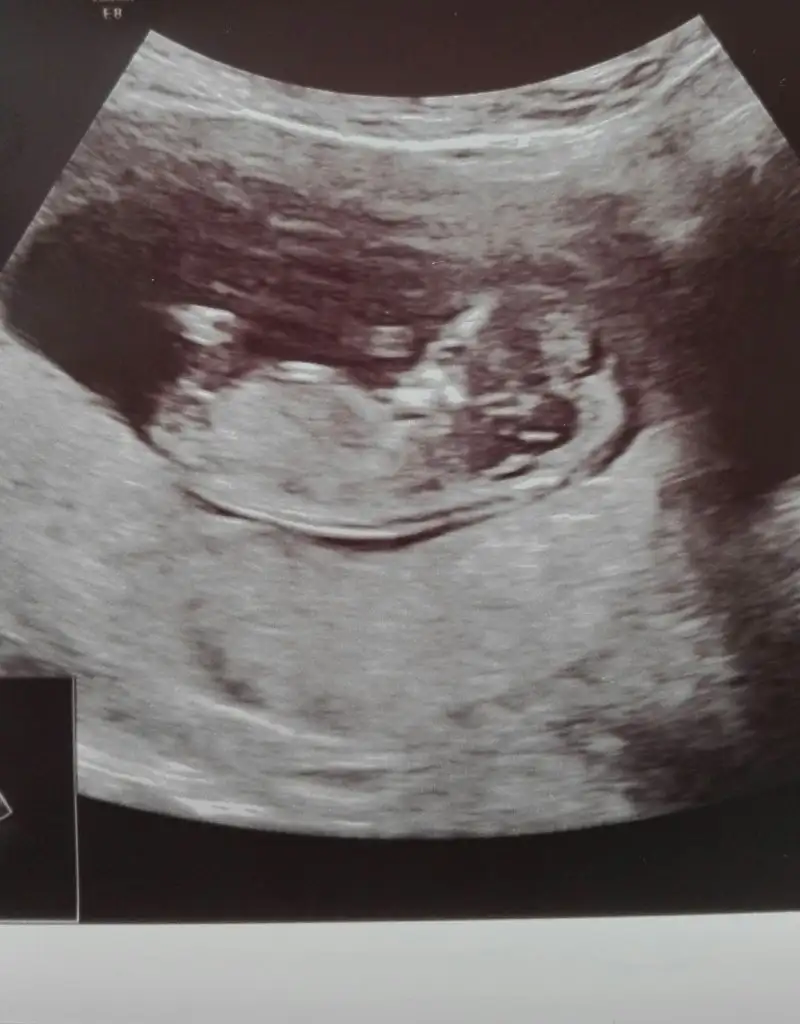

Cinsiyetler yavaş yavaş çıkıyor daha bir heyecan oluyor en azından ismi ile severim fıstığım derim yakışıklım derim inşallah ikisini birden derim

Yaa bide sen tecrubelisin bu konudaBen kendi Oğlumun ultrason görüntüsüne benzetim

Benim de içime erkek gibi doğduKizlar sizce bebisimin cinsiyeti neEki Görüntüle 2561424

Cinsiyeti öğrendin mi canım. Maşallah ultrasonda tam bir bebek hatlarında görünmüş. Ben de görmek istiyorum ayInsallah bir kiz bir erkek saglikla olur canim

Canm kac haftalksn masallaj tam bebek olmsKizlar sizce bebisimin cinsiyeti neEki Görüntüle 2561424